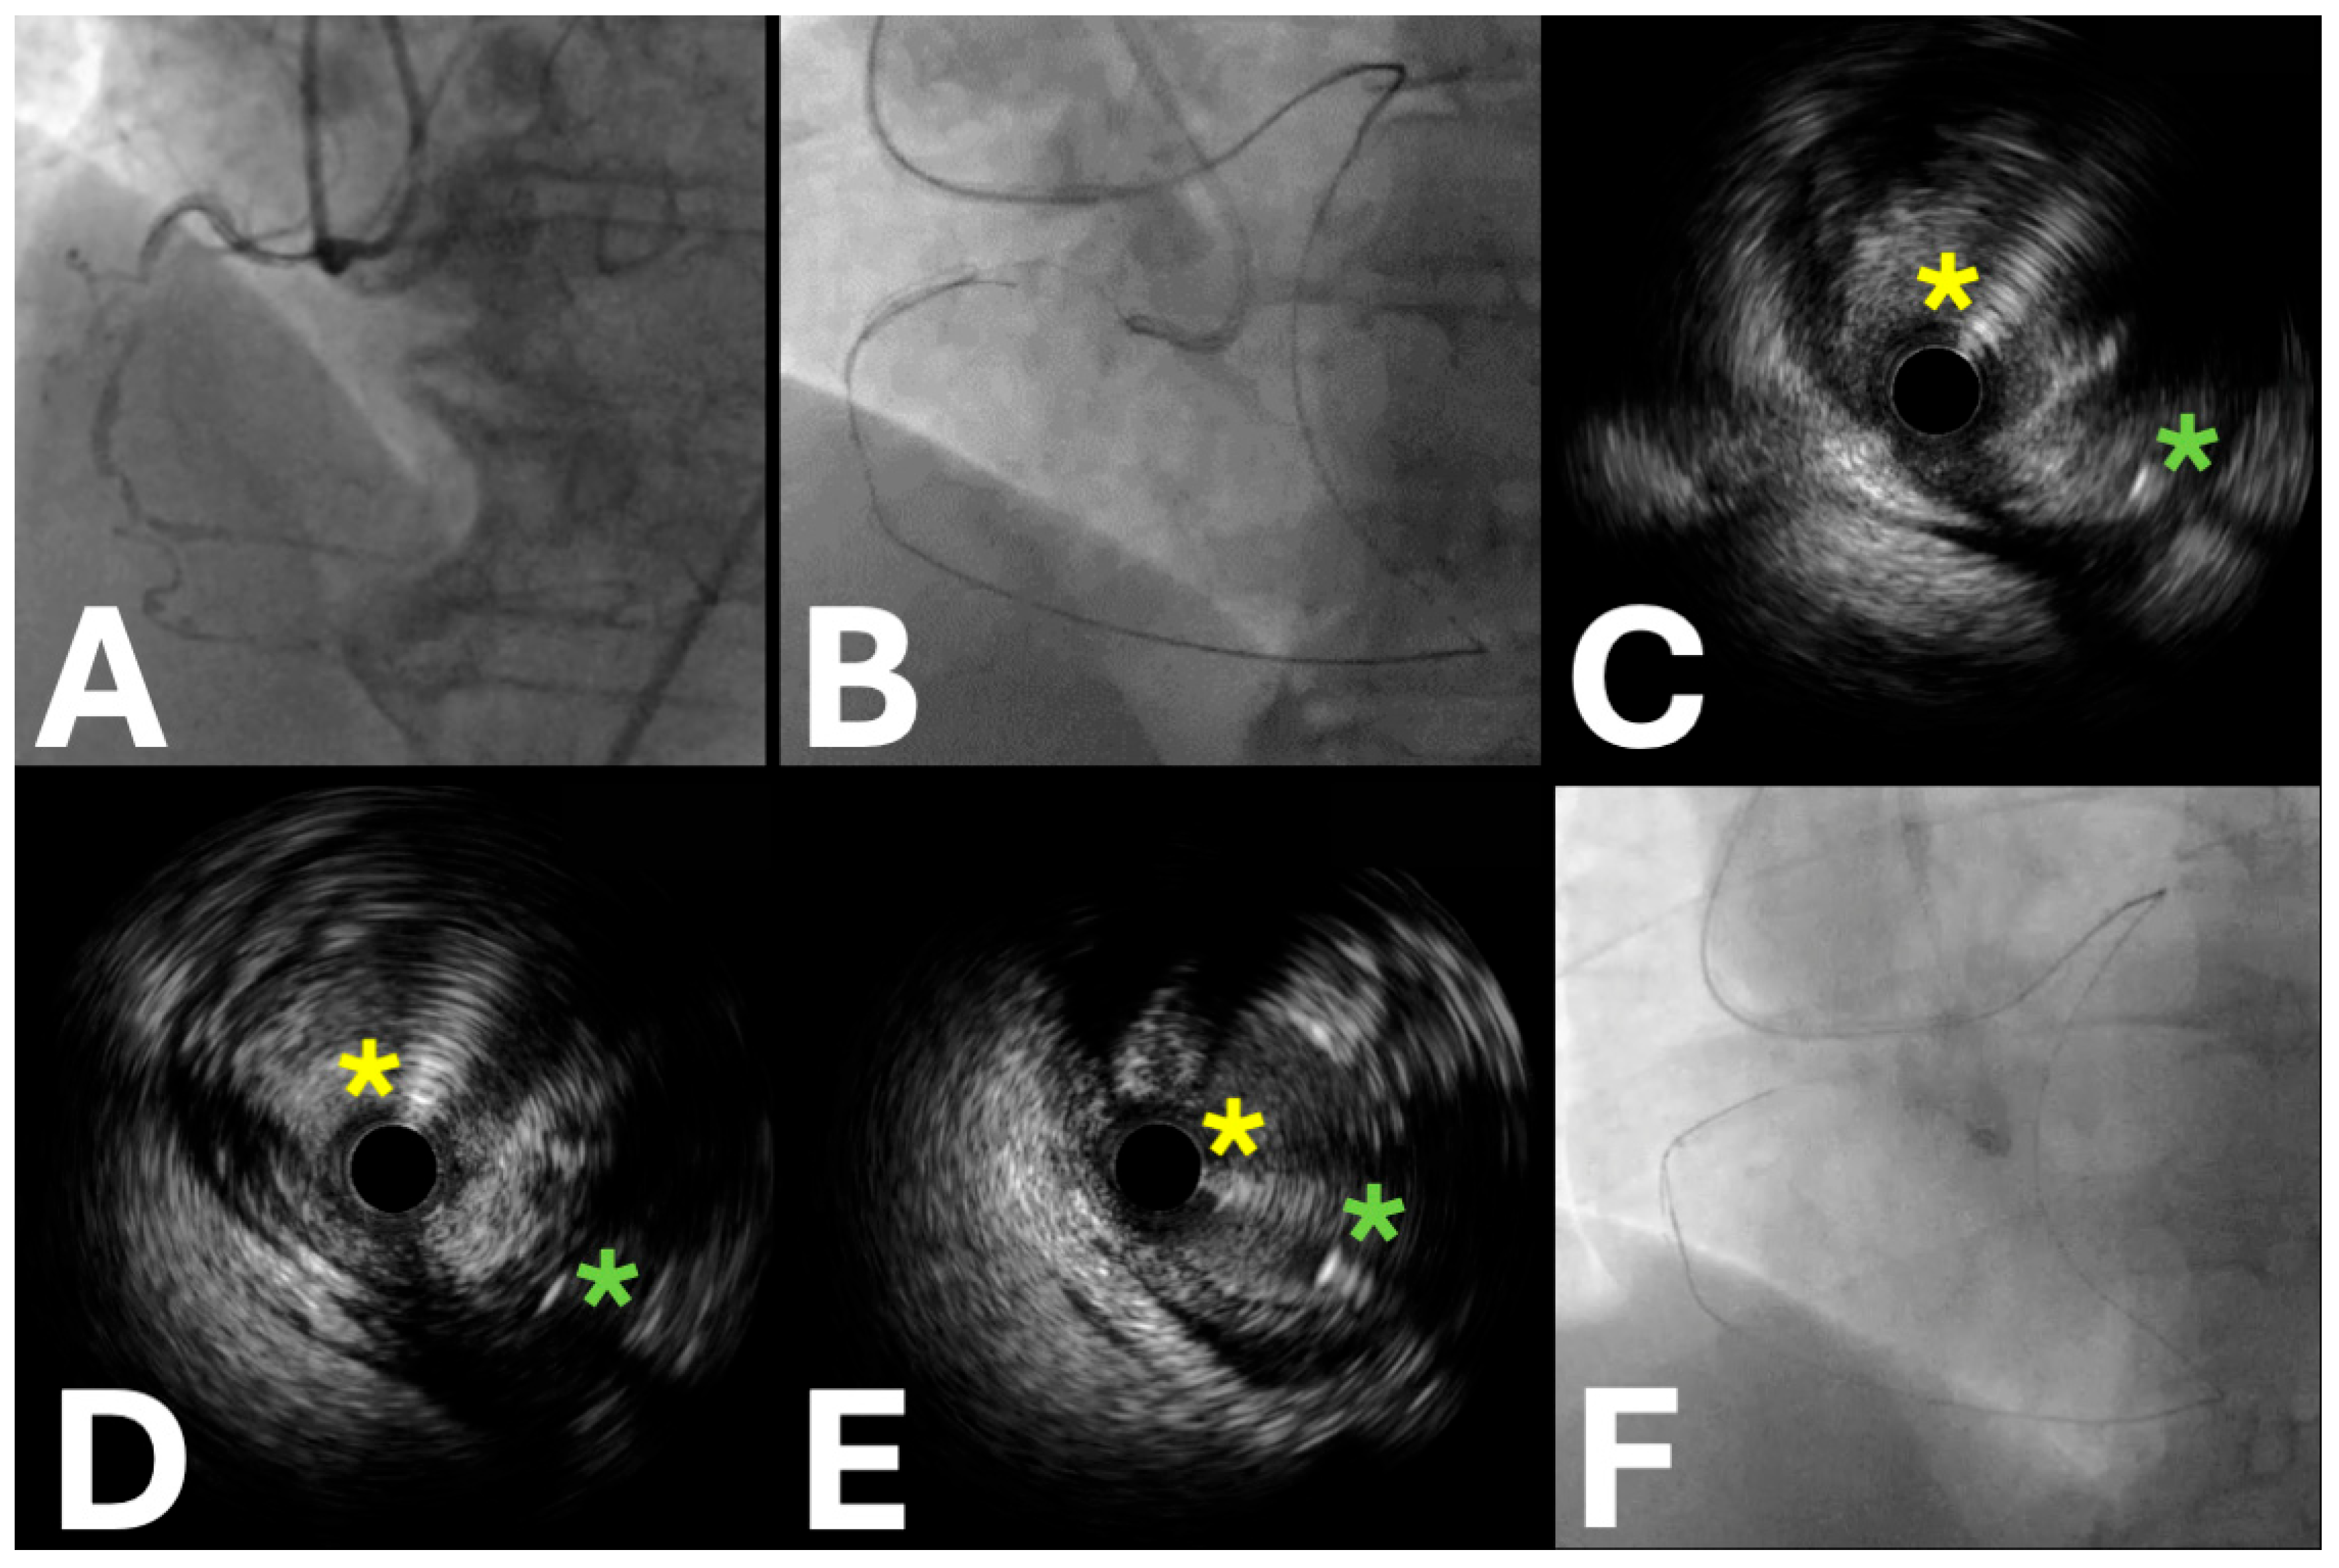

- Proximal cap puncture

- Antegrade wiring

- Antegrade dissection and re-entry

2.2. IVUS Applications in the Retrograde Approach

- Retrograde wiring

- Reverse controlled antegrade retrograde tracking